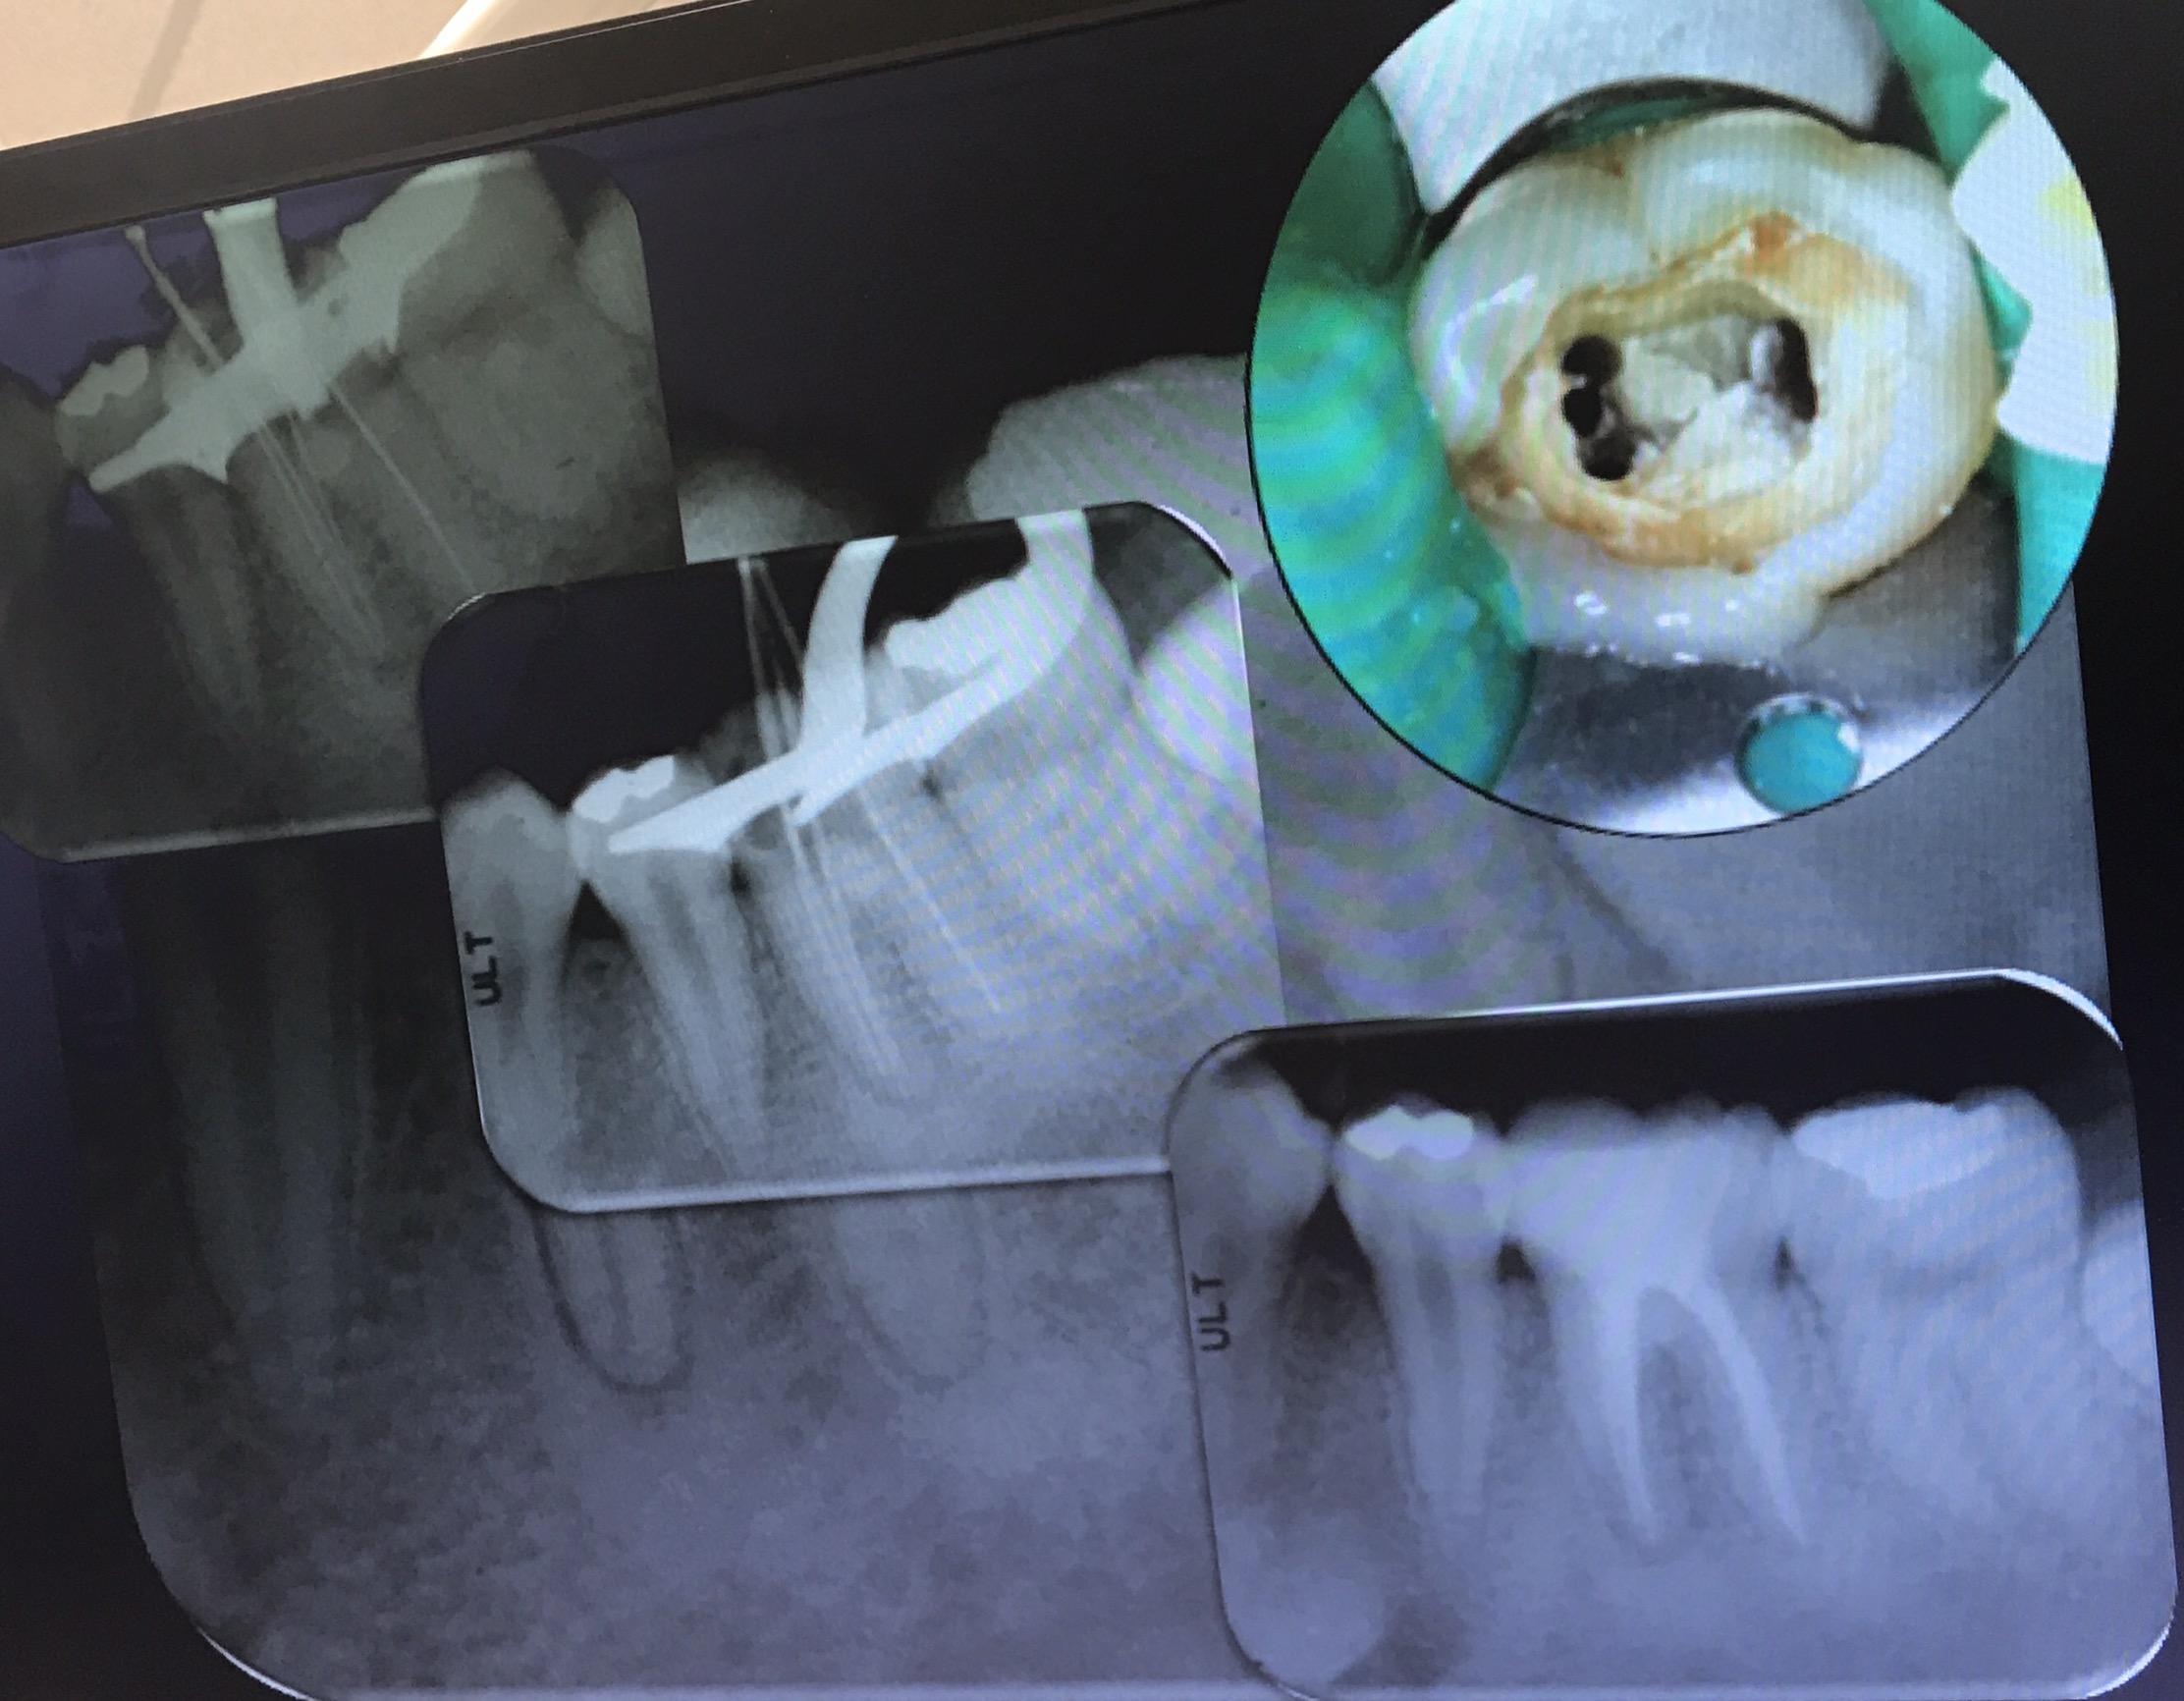

อันนี้คือ case จริงครับ ส่วนที่ Outline ไว้ตรงกลางคือ รอย Perforate

repair ใช้ MTA และ wet cotton (เพื่อให้ set)

อีก case

จุดสีเหลือง คือ canal ที่ถูกต้อง

วงกลมสีแดง แสดงส่วนที่ถูก repair ด้วย MTA

การ repair โดยใช้ Internal matrix

Internal matrix คือการใช้วัสดุปิดชั้นแรกสุดเข้าไปก่อน เพือป้องกันวัสดุอีกตัวที่ใช้ repair ไม่ให้รั่วไหลออกมา

วัสดุที่ใช้เป็น matrix ชั้นแรก Collaplug

หน้าที่คือ stop bleed เป็น matrix ล้อมรอบ MTA หรือ Biodentine ไว้ ไม่ให้ออกนอก canal

อันนี้คือ แบบฝึกหัดใน lab ครับ